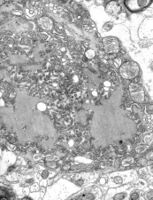

TEM micrograph with numerous rabies virions (small, dark grey, rodlike particles) and Negri bodies (the larger pathognomonic cellular inclusions of rabies infection)

The rabies virus is the type species of the Lyssavirus genus, in the family Rhabdoviridae, order Mononegavirales. Lyssavirions have helical symmetry, with a length of about 180 nm and a cross-section of about 75 nm.[33] These virions are enveloped and have a single-stranded RNA genome with negative sense. The genetic information is packed as a ribonucleoprotein complex in which RNA is tightly bound by the viral nucleoprotein. The RNA genome of the virus encodes five genes whose order is highly conserved: nucleoprotein (N), phosphoprotein (P), matrix protein (M), glycoprotein (G), and the viral RNA polymerase (L).[34]

Rabies can be difficult to diagnose because, in the early stages, it is easily confused with other diseases or even with a simple aggressive temperament.[60] The reference method for diagnosing rabies is the fluorescent antibody test (FAT), an immunohistochemistry procedure, which is recommended by the World Health Organization (WHO).[61] The FAT relies on the ability of a detector molecule (usually fluorescein isothiocyanate) coupled with a rabies-specific antibody, forming a conjugate, to bind to and allow the visualisation of rabies antigen using fluorescent microscopy techniques. Microscopic analysis of samples is the only direct method that allows for the identification of rabies virus-specific antigen in a short time and at a reduced cost, irrespective of geographical origin and status of the host. It has to be regarded as the first step in diagnostic procedures for all laboratories. Autolysed samples can, however, reduce the sensitivity and specificity of the FAT.[62] The RT PCR assays proved to be a sensitive and specific tool for routine diagnostic purposes,[63] particularly in decomposed samples[64] or archival specimens.[65] The diagnosis can be reliably made from brain samples taken after death. The diagnosis can also be made from saliva, urine, and cerebrospinal fluid samples, but this is not as sensitive or reliable as brain samples.[62] Cerebral inclusion bodies called Negri bodies are 100% diagnostic for rabies infection but are found in only about 80% of cases.[33] If possible, the animal from which the bite was received should also be examined for rabies.[66]